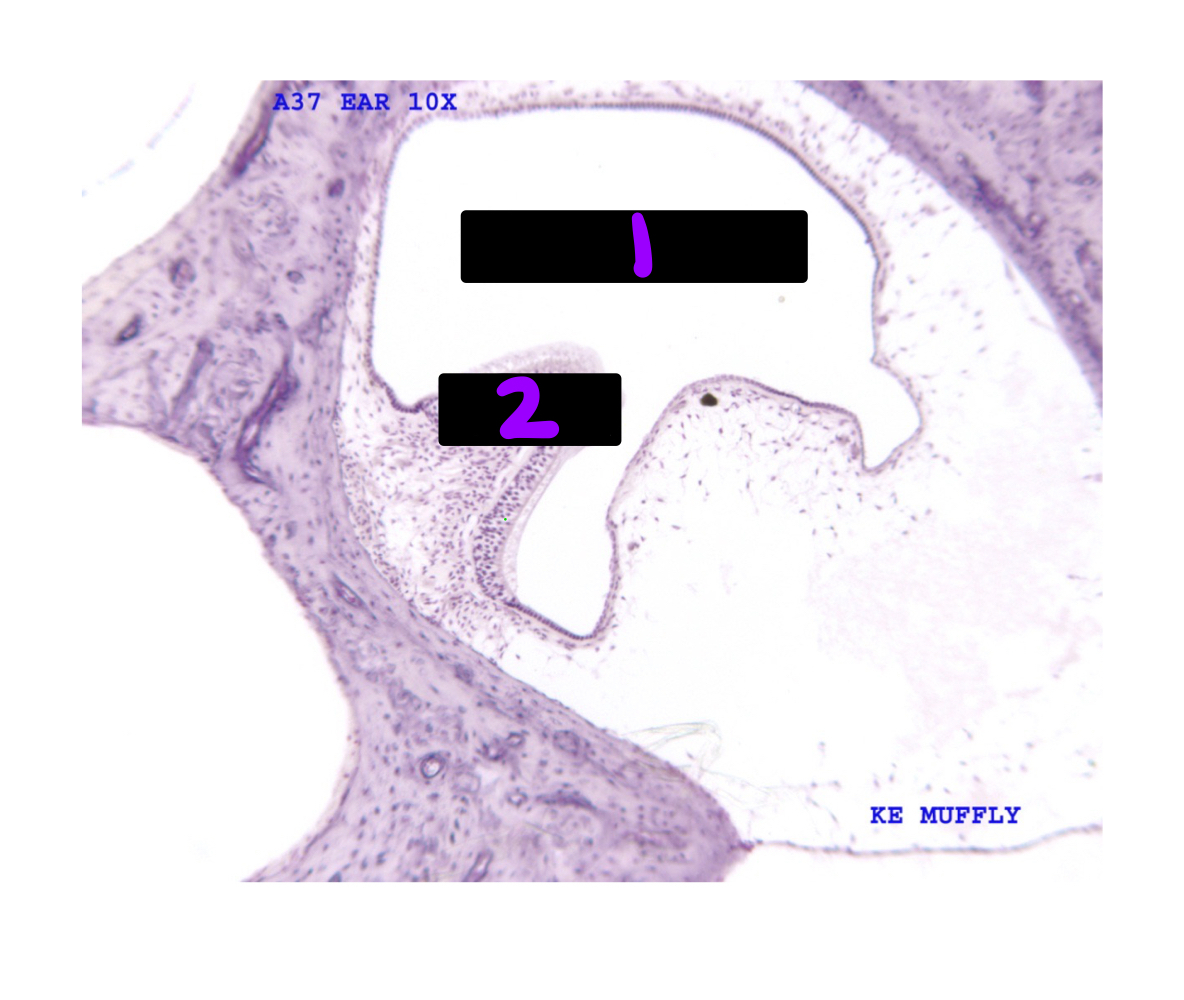

Q

What is #1 and 2?

A

1. Ampula of semicircular canal with endolymph

2.cupula